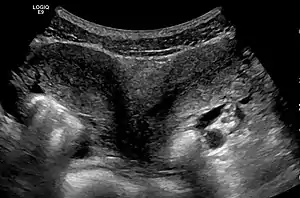

| Ultrasound showing didelphys | |